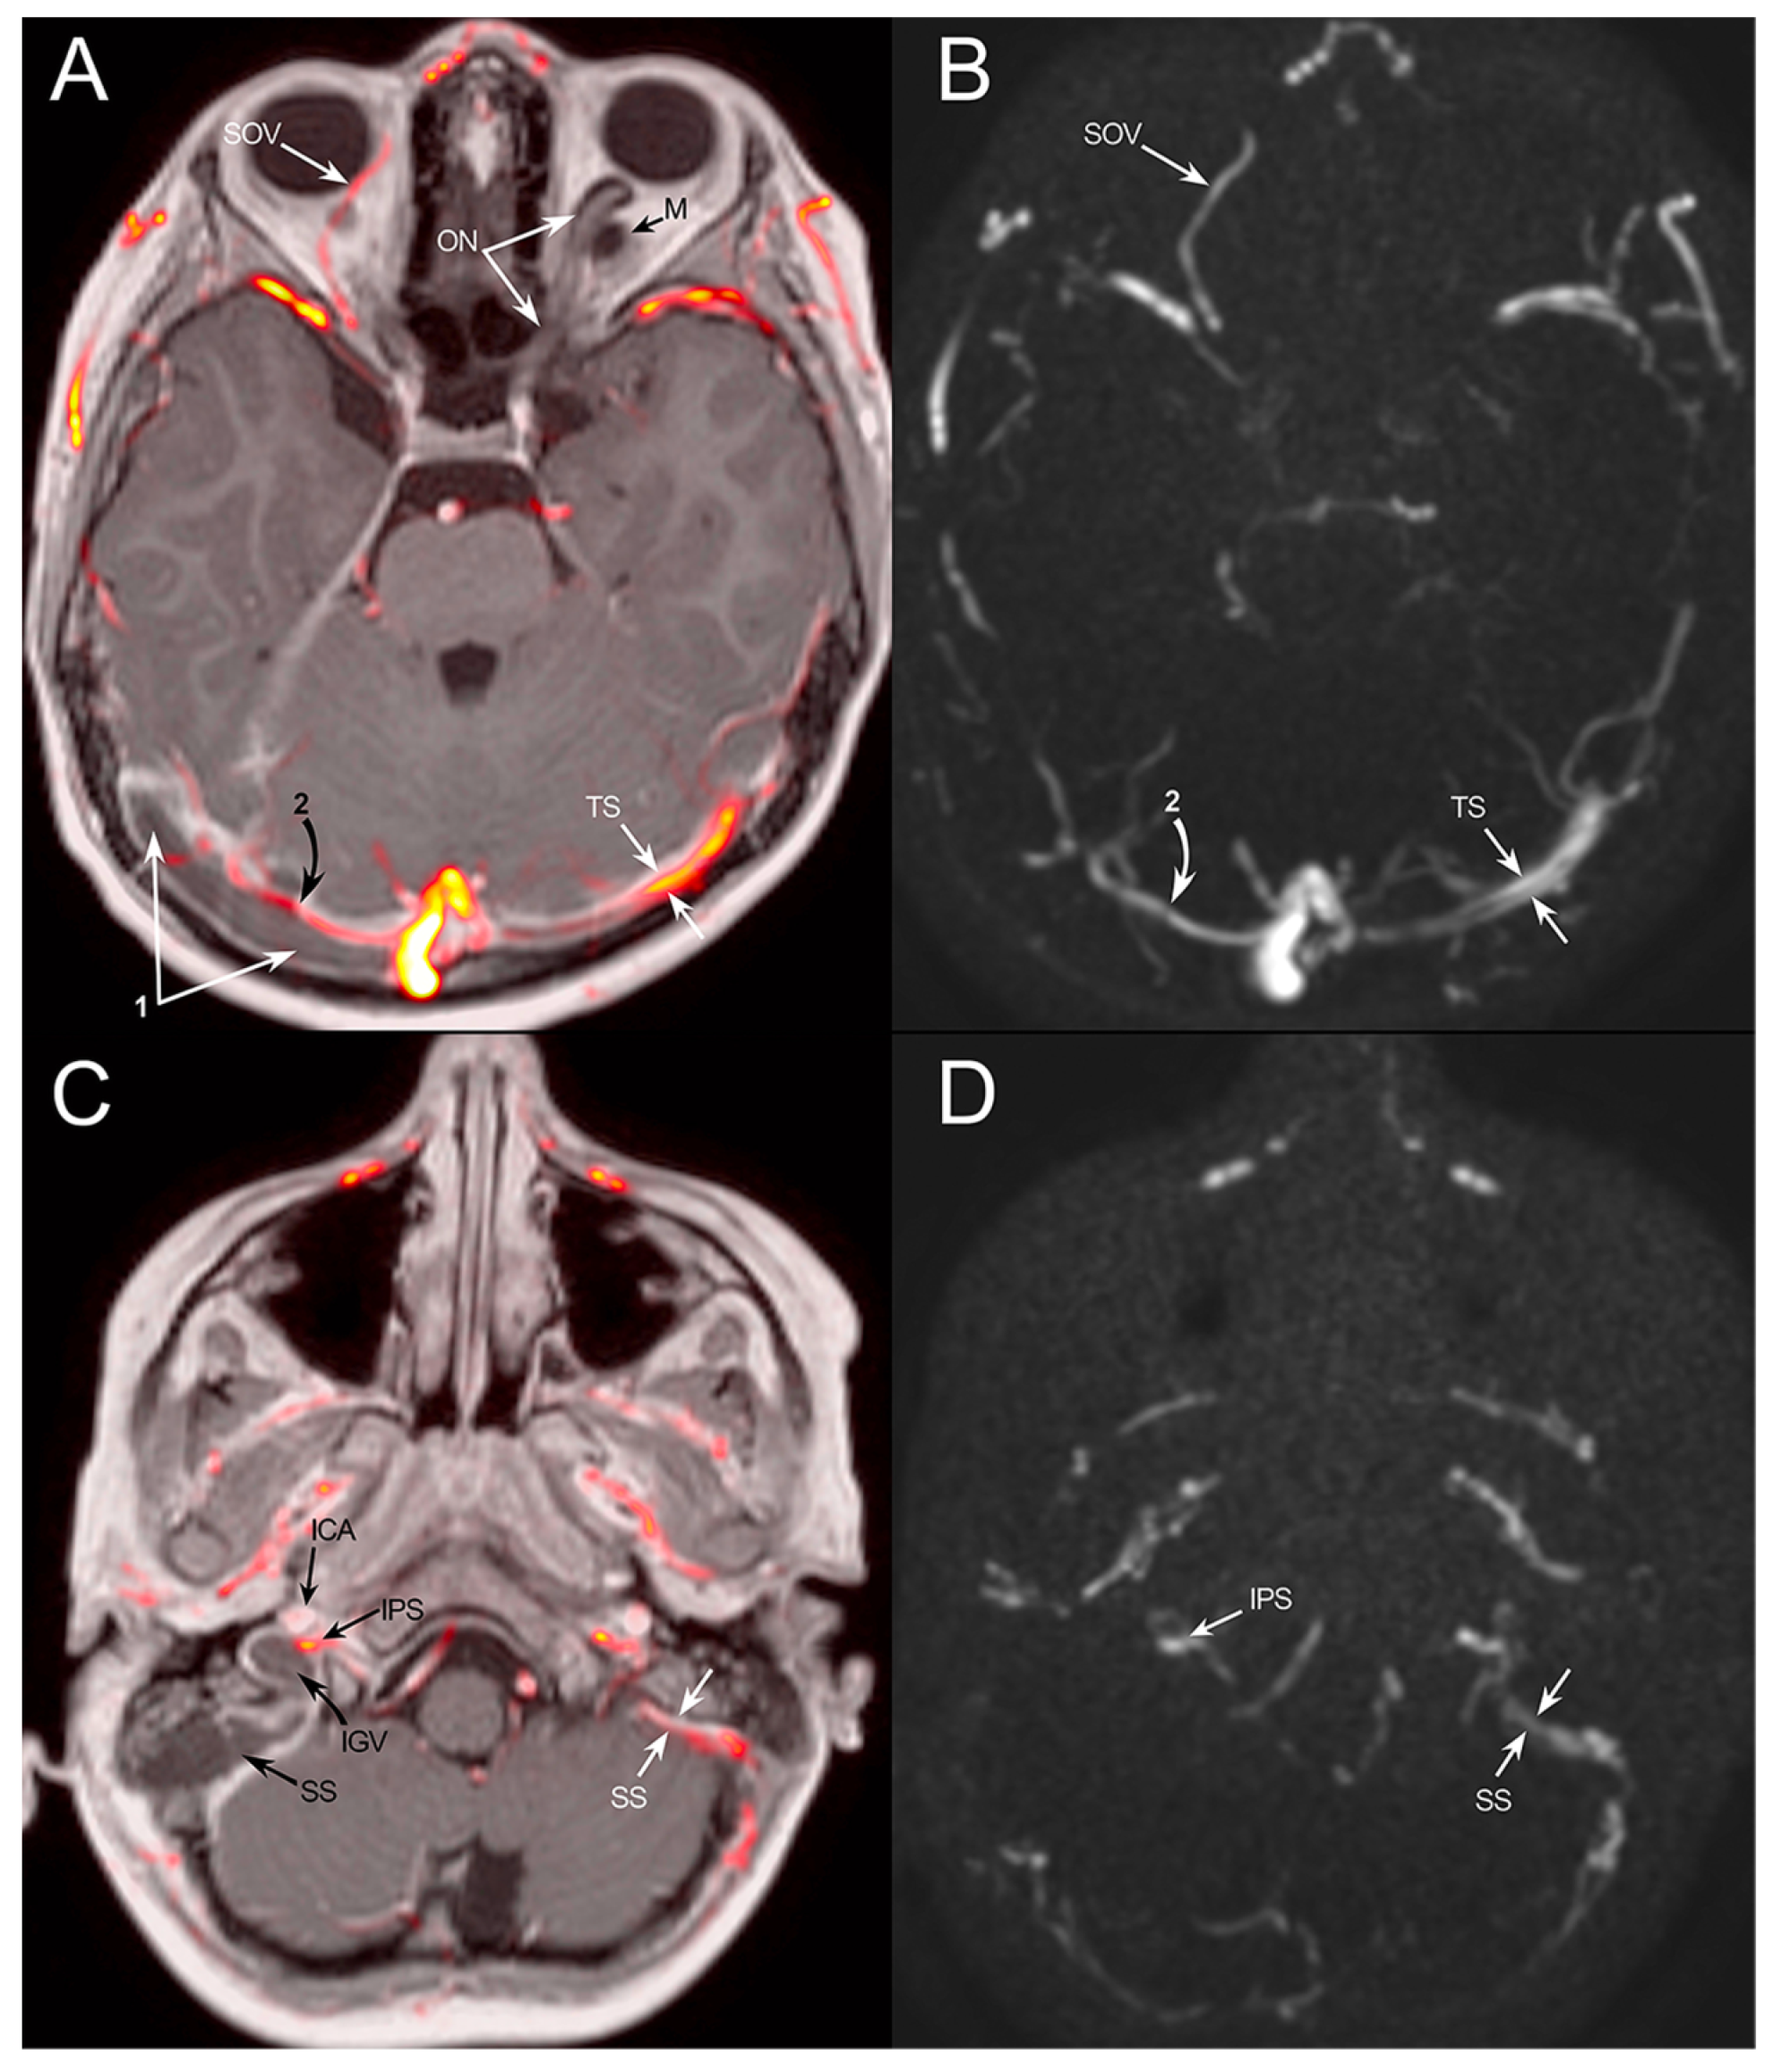

3.1. Case Report